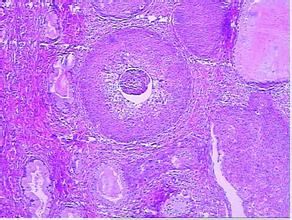

1.癌前期皮肤病 某些癌前期皮肤病如日光角化病、黏膜白斑、砷角化病、X线和镭射线性皮炎等均易致鳞癌。以及其他慢性皮肤病,如疣状表皮发育不良、慢性溃疡、慢性窦道、慢性骨髓炎、慢性红斑狼疮、寻常狼疮、萎缩硬化性苔藓等均可诱发或继发鳞癌。

4.继发于慢性皮肤病变 某些慢性皮肤病,如寻常狼疮、红斑狼疮、黏膜白斑、慢性溃疡或窦道、烧伤瘢痕、射线皮炎、慢性肉芽肿疣状表皮发育不良、慢性骨髓炎、萎缩硬化性苔藓等均可诱发或继发鳞癌。